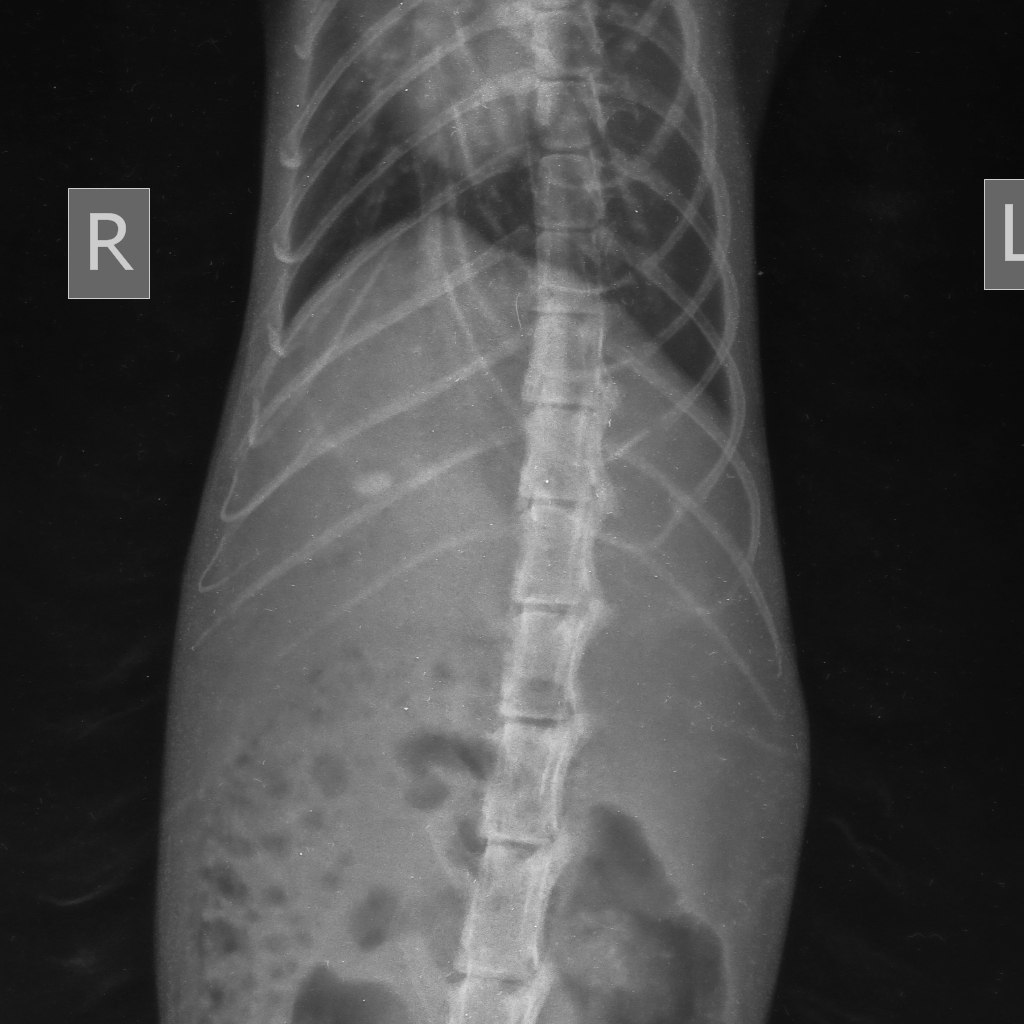

Рентгенография (рис.2) может выявить только рентген контрастные камни: холестериновые холелиты рентген прозрачны!

Рис.2. Рентгена контрастный холелит в проекции желчного пузыря